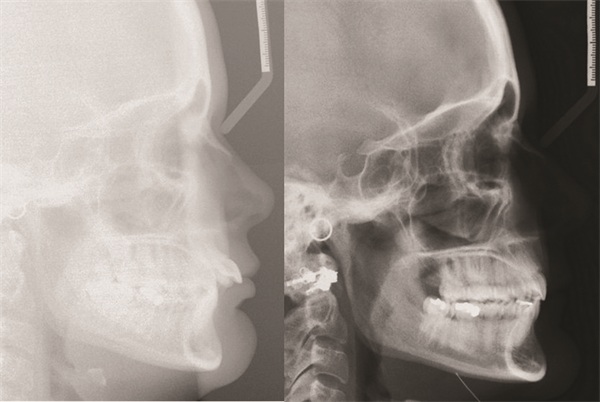

Fig. 1

Late into Tara’s treatment in 2020, I had just begun looking at my cases from an “outside-in” perspective, with an emphasis on prioritizing macro-aesthetic facial features when evaluating all pre-treatment and post-treatment records. This was in large part because of my lengthy time away from practice during the COVID-19 shutdown, which allowed me to read Dr. David Sarver’s book Dentofacial Esthetics: From Macro to Micro. It’s the only book I’ve ever read that I immediately began rereading after finishing.

With a new perspective, I evaluated Tara’s treatment outcome. While I was still satisfied with many aspects of the final results, I was not nearly as happy with the subtle but noticeable change to her soft-tissue facial profile, particularly her lips and circumoral presentation. The amount of incisor retraction achieved through our treatment was more than enough to address the chief complaint of flared teeth, but it also, in my view, went a bit too far in reducing the fullness and forward position of her lips.

Yes, some degree of lip retraction was indicated based on the mild lip incompetence shown in the pretreatment records, but it seemed to me that I had overshot it. Outside of just the lips, her circumoral volume also seemed more deflated or sunken. Her final photos show more pronounced nasolabial folds, downward lateral commissures, and the appearance of marionette lines. Additionally, her chin projection, because of her retracted lips, now appeared relatively more forward. To me, the treatment that took two years appeared to have taken 10 years.